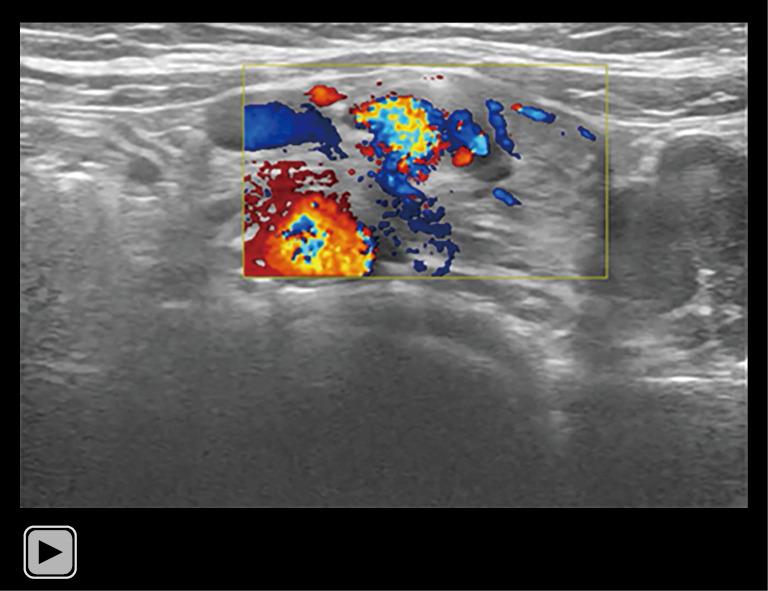

Congenital duodenal obstruction (CDO) is commonly detected antenatally through the presence of the "double bubble" sign on prenatal ultrasound, denoting dilatation of the stomach and duodenum. Subsequent postnatal ultrasonography plays a pivotal role in determining the causes of obstruction, thereby informing surgical strategies and neonatal management. The aim of this study was to investigate the diagnostic accuracy of postnatal ultrasonography in comparison to that of prenatal ultrasound and surgical findings in a cohort of 43 patients with fetal double bubble sign.

The accuracy rates for prenatal and postnatal ultrasonic diagnosis of CDO were 97.7% (42/43) and 100% (42/42), respectively. In terms of etiological diagnosis, prenatal and postnatal ultrasound correctly identified the causes of obstruction in 45.2% (19/42) and 81.0% (34/42) of cases, respectively, as confirmed by surgical intervention.

先天性十二指肠梗阻(CDO)通常在产前通过产前超声检查发现的“双泡征”来检测,该征表示胃和十二指肠扩张。随后的产后超声检查在确定梗阻原因方面起着关键作用,从而为手术策略和新生儿管理提供依据。本研究的目的是在一组43例有胎儿双泡征的患者中,比较产后超声检查与产前超声检查及手术结果的诊断准确性。

产前和产后超声诊断CDO的准确率分别为97.7%(42/43)和100%(42/42)。在病因诊断方面,经手术干预证实,产前和产后超声分别在45.2%(19/42)和81.0%(34/42)的病例中正确识别了梗阻原因。